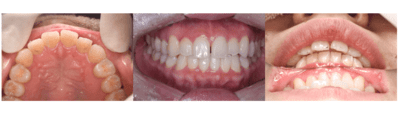

治療前

治療後